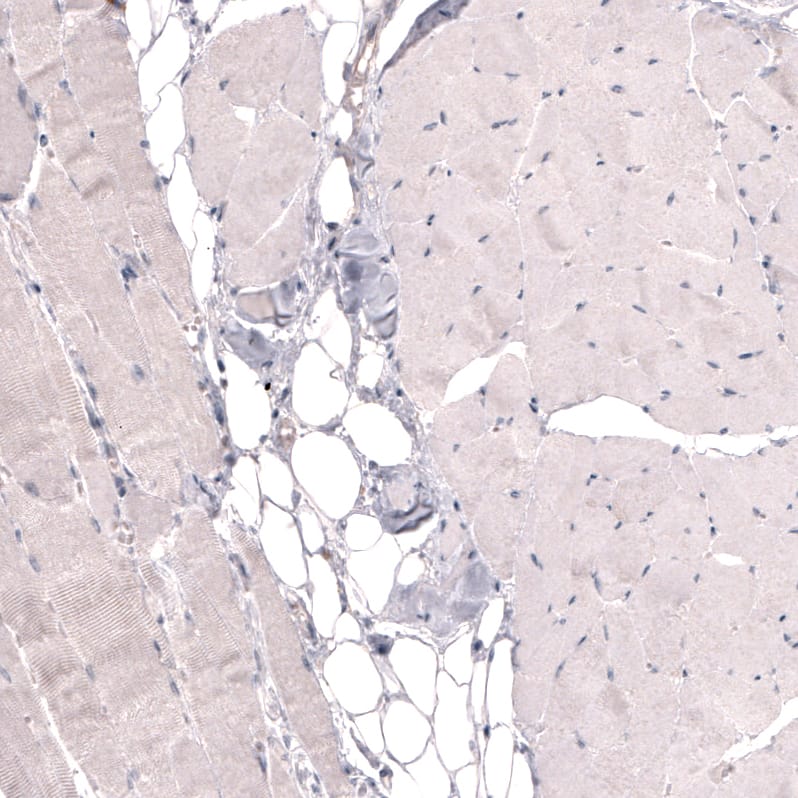

Orthogonal Strategies: Analysis in human kidney and skeletal muscle tissues using NBP3-44072 antibody. Corresponding THSD7A RNA-seq data are presented for the same tissues.

Staining of human skeletal muscle shows no positivity in striated muscle fibers as expected.